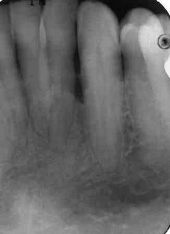

moderate to severe horizontal bone loss

advanced stages of perio

extensive horizontal bone loss or extensive vertical defects

osseous defects in furcation of multirooted teeth

floating tooth